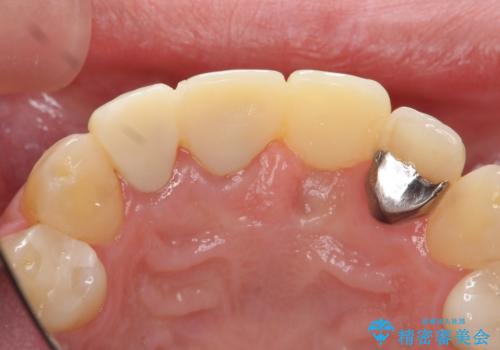

左側の前歯には他院で埋入されたポジションの悪いインプラント補綴により歯冠長の長いクラウンが装着されており、感染による排膿も認められこのまま審美性を改善するのは難しい状態です。